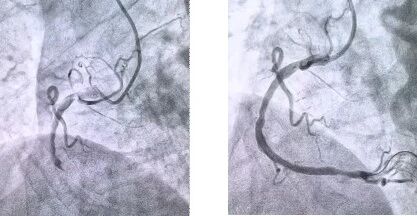

患者抵達(dá)醫(yī)院后,簡化掛號、繳費(fèi)等中間環(huán)節(jié),迅速溝通病情,需要緊急介入治療,獲得家屬同意,立即送至導(dǎo)管室。造影顯示其右冠狀動(dòng)脈中段完全閉塞,醫(yī)生迅速實(shí)施血栓抽吸,球囊擴(kuò)張和藥物洗脫支架植入術(shù)。36 分鐘后,閉塞血管恢復(fù)正常血流,吳大爺?shù)难獕骸⑿穆手饾u平穩(wěn),胸痛癥狀明顯緩解。術(shù)后三天,他便轉(zhuǎn)入普通病房進(jìn)行康復(fù)訓(xùn)練,重拾健康生活。